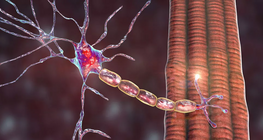

Functionally the three main roles of the nervous system are sensation, integration, and response.